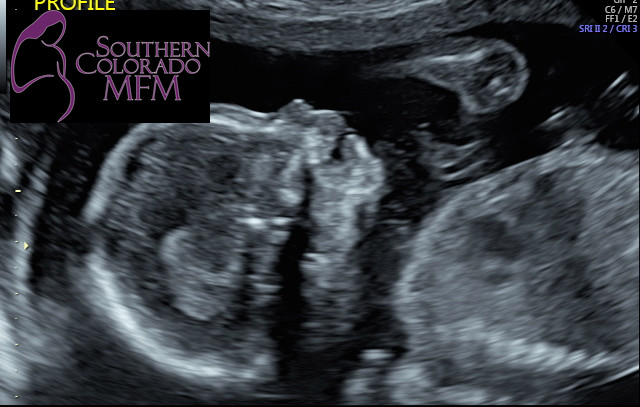

2nd: Diagnosis